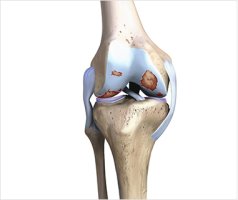

연골은 뼈와 관절을 보호하는 데 중요한 역할을 하는데 이런 연골은 우리가 걷고 움직일 때 큰 도움이 돼요. 스포츠 뉴스에서 TV 오락 프로그램에 나오는 운동선수들이 운동량이 너무 많고 부상도 많아 연골이 닳았다는 말을 자주 듣습니다.

연골은 나이가 들면서 닳아 없어지지만 운동량이 많은 운동선수에서는 속도가 빨라지기 때문에 젊은 나이에도 연골이 심하게 닳거나 빠지는 경우가 많아요. 연골이 없거나 연골이 닳으면 몸의 유연성이 떨어지고 관절 통증이 생깁니다.

연골의 주성분인 콘드로이친이 관절의 간극을 유지시켜주고 연골이 마모되는 것을 막아줘요. 노인의 노화 과정에서 콘드로이친이 감소함에 따라 연골의 뼈와 뼈 사이의 완충 효과와 보호 기능이 급격히 악화돼요. 부족한 콘드로이친 주사를 통해 연골의 마모를 늦추는 것이 관절염 예방과 해결의 큰 법칙입니다.

또 콘드로이친은 퇴화된 관절세포를 재생하는 데 중요한 역할을 한다고 합니다. 미국의 한 연구에서 한동안 골관절염 환자의 골관절염 통증 관리에 대한 콘드로이친의 효과를 관찰한 결과 약 10%가 통증 감소 및 개선 효과를 보였어요. 관절통이 있으시다면 복용하시면 좋을 것 같아요.